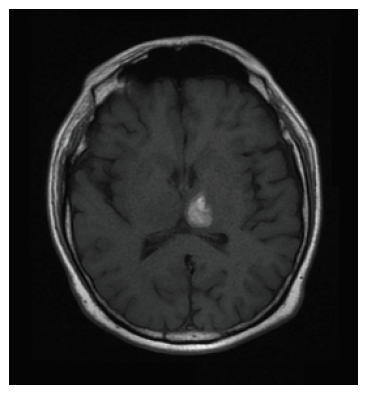

Se reporta ecografía de vasos carotideos sin compromiso hemodinámico cerebral. La RMN evidenció hematoma intraparenquimatoso de ubicación talámico-izquierda (figura 2). La panangiografía cerebral no reveló hallazgos patológicos. Se decide un tratamiento conservador y monitorización neurológica. Transcurrido el tercer día de hospitalización, el paciente recuperó la totalidad de sus funciones neuropsicológicas sin secuelas. Durante los siguientes tres días de hospitalización el paciente continuó su evolución de manera satisfactoria. Se dio de alta médica con recomendaciones y manejo sintomático. No obstante, continúa en seguimiento periódico por parte del Departamento de Neurología.

Figura 1 A, B y C: TAC de cráneo simple (corte sagital, coronal y axial) que evidencia hematoma de ubicación talámico izquierdo con diámetro máximo de 16 x 15 mm que estaría en relación a hematoma intraparenquimatoso